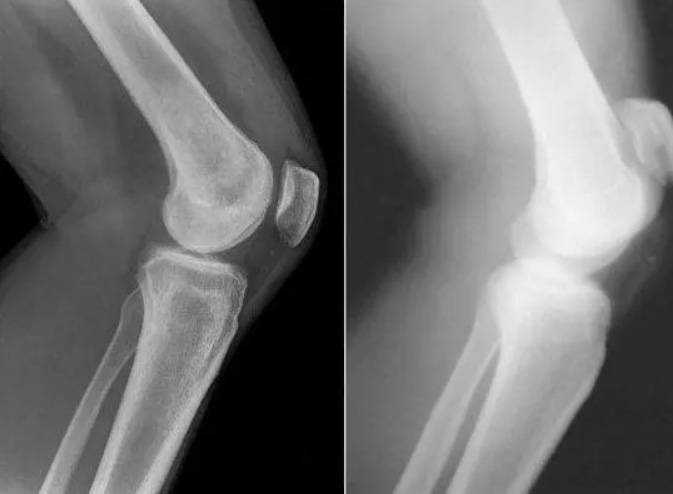

Restauration de l'articulation du coude. Patiente, 31 ans. Durée du traitement par la Marukaya Cream : 12 jours. Son articulation est entièrement restaurée :